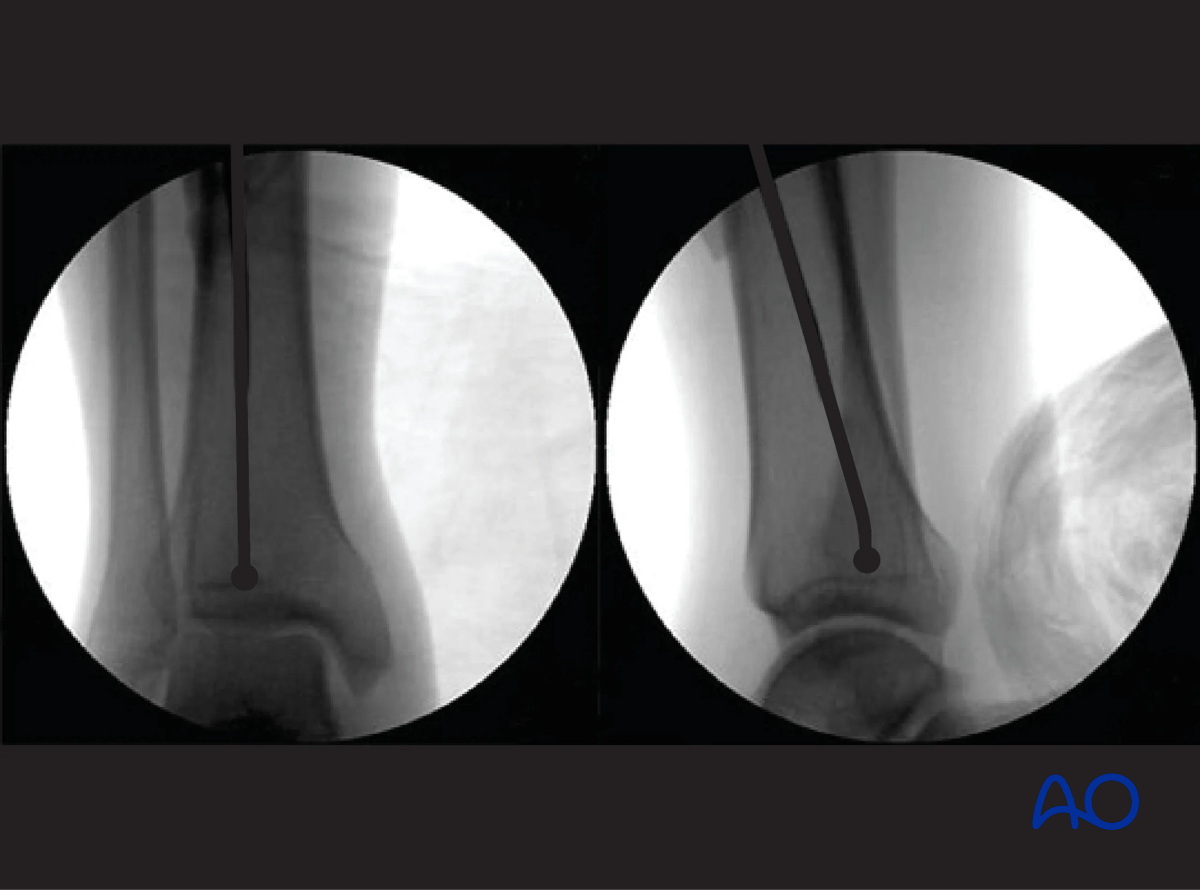

Once the proximal tibia has been prepared with the entry reamer, the initial guide wire is removed, and a ball-tipped guide wire is carefully tapped down the medullary canal to the distal metaphysis. This requires fracture reduction. If reduction is difficult or the fracture is comminuted, special efforts may be required.

Slightly bending the guide wire 10–15 mm above its tip is helpful for the following reasons:

Do not bend the guide wire excessively or the reamer and/or nail will become incarcerated in the guide wire.

Use fluoroscopy to check that the guide wire is positioned above the center of the ankle joint.

Ensure a proper AP and lateral image of the ankle is taken. The end of the ball-tip guide wire should be seated at or just above the level of the epiphyseal scar. This is especially the case for more distal fractures of the tibia.